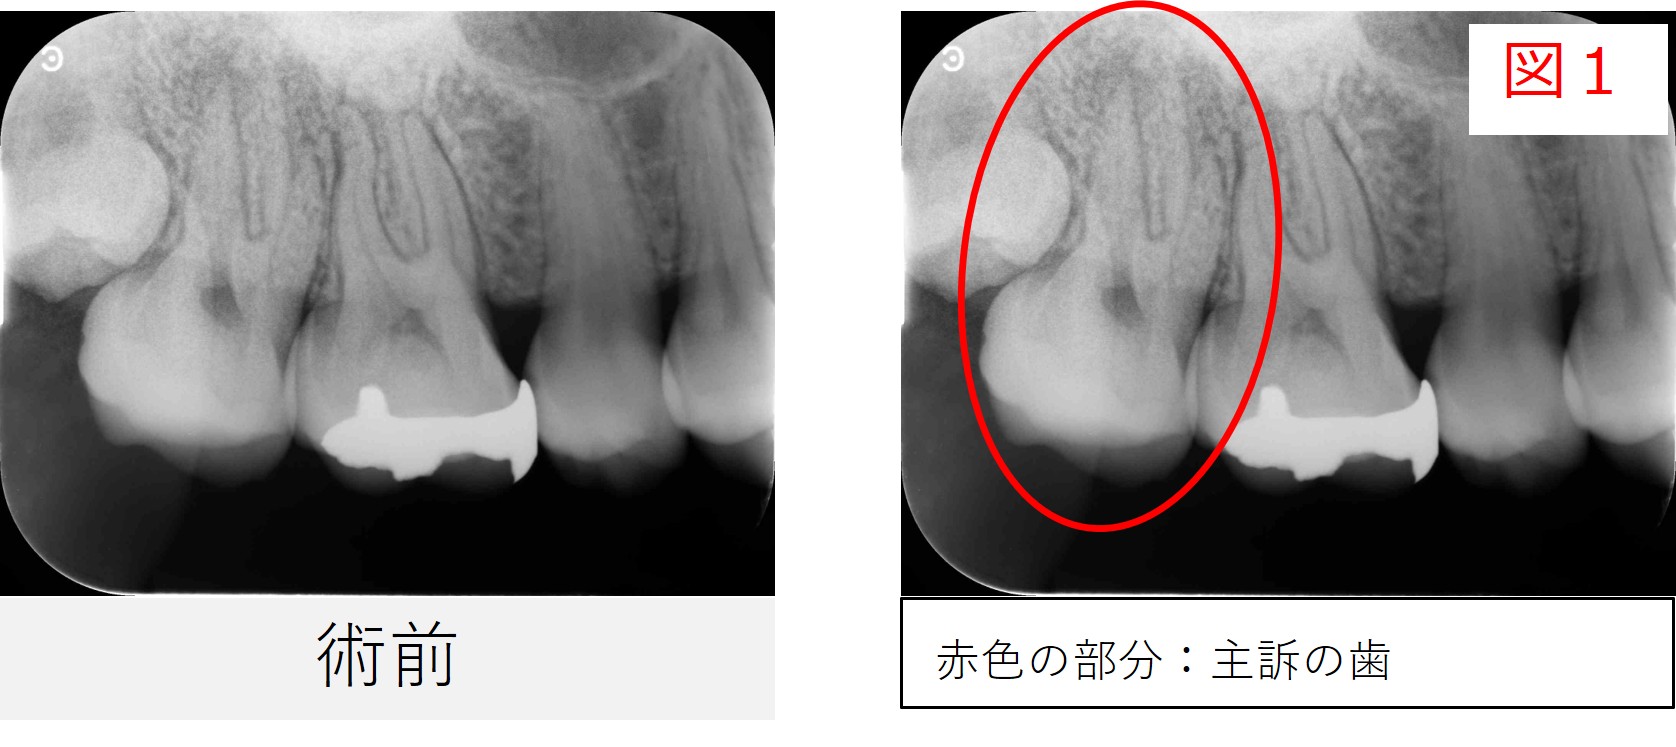

●レントゲン・CT画像所見

レントゲンでは、**右上6番と7番のどちらにも根の先に透過像(黒い影)**が見られました。

この段階では、どちらの歯が原因となっているのかは判断が難しい状況でした。

しかし、CT画像で詳細に確認すると、右上7番の根の先にある透過像(黒い影)がより明瞭で、炎症が右上6番の方向へ広がっているように見えました。

また、右上7番は根の形が緩やかに曲がった(湾曲した)形態をしており、根の通り道がまっすぐではないことも確認されました。